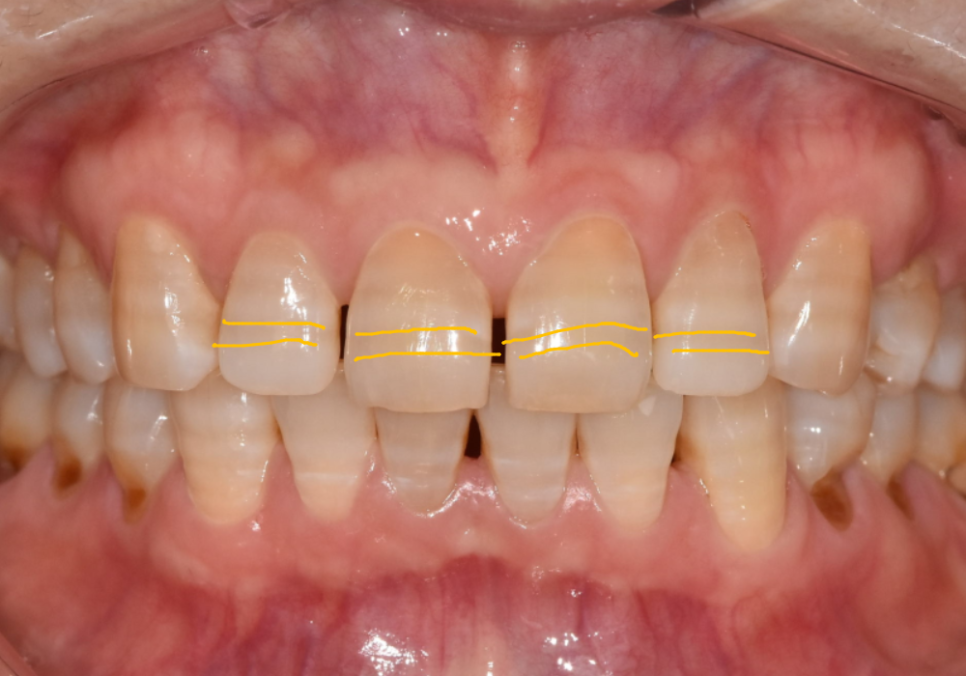

앞니 변색, 치아미백효과 없는 이유

갈색이나 회색 띠가 가로로

나타나는 것이 특징입니다.

이런 변색은 치아 표면이 아니라

내부 상아질에 색소가 침착되어 있어서

미백제로는 개선이 힘듭니다.